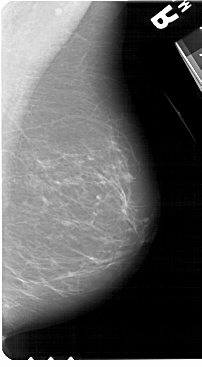

A_1273_1.LEFT_MLO

LEFT_MLO LINES 5491 PIXELS_PER_LINE 3511 BITS_PER_PIXEL 12 RESOLUTION 43.5 OVERLAY